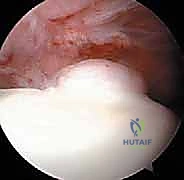

الخطوة 5: إصلاح الشفا الحقي (Labral Repair)

إذا كان الشفا الحقي ممزقاً (وهو أمر شائع جداً)، لا يتم استئصاله، بل يحرص الدكتور هطيف على إصلاحه للحفاظ على وظيفة المفصل. يتم ذلك باستخدام "خطاطيف خياطة" (Suture Anchors) صغيرة جداً تُزرع في العظم وتُستخدم لربط وخياطة الشفا وإعادته لمكانه الطبيعي.